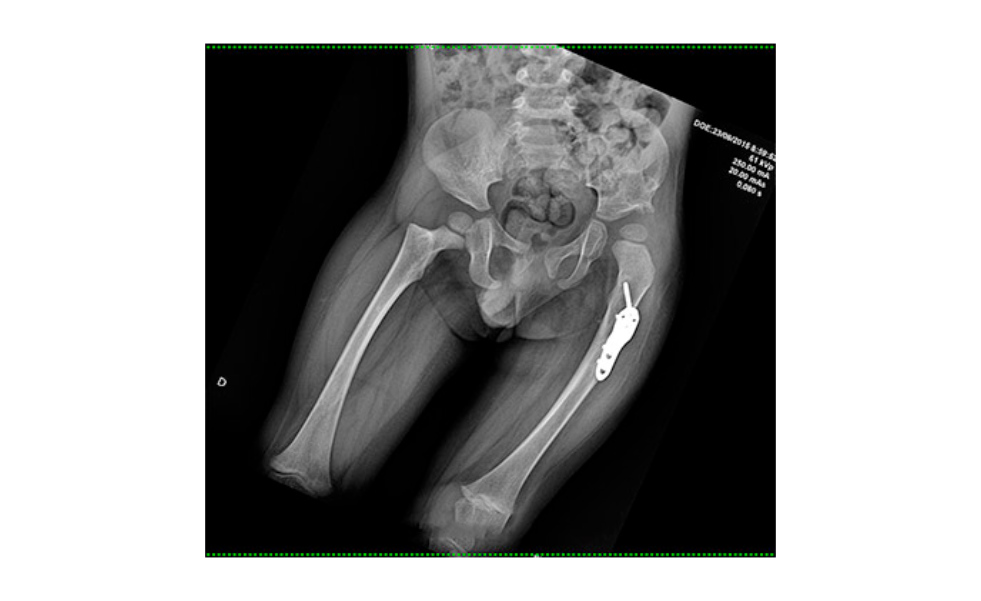

Hoy tienen 2 años y 8 meses. La cadera izquierda de Juan Andrés ya está estable y como parte del plan para lograr su funcionalidad y marcha, a Juanchi le correspondió su segunda cirugía, la cual fue realizada por su mismo médico tratante, quien ahora está radicado y ejerciendo en esta hermosa ciudad. El equipo quirúrgico del Dr. Galbán y el Dr. Mora han adecuado sus miembros inferiores mediante 8 procedimientos operatorios en un solo tiempo quirúrgico para que cumpla su sueño de caminar.

La cirugía de la luxación de cadera izquierda se realizó mediante la técnica de SuperHip descrita por el Dr Dror Paley y resultó un éxito, pero las afectaciones neurológicas de la mielodisplasia se presentan en él con un patrón bajo, pero asimétrico. Esto produjo un gran obstáculo para la bipedestación y mucho más para la marcha, en otras palabras no podía pararse derecho y mucho menos caminar. La cirugía realizada en la Clinica el Rosario El Tesoro logró mediante una serie de osteotomías y transferencias tendinosas balancear sus miembros inferiores para que Juanchi logre la bipedestación y pueda con entrenamiento la tan deseada marcha.